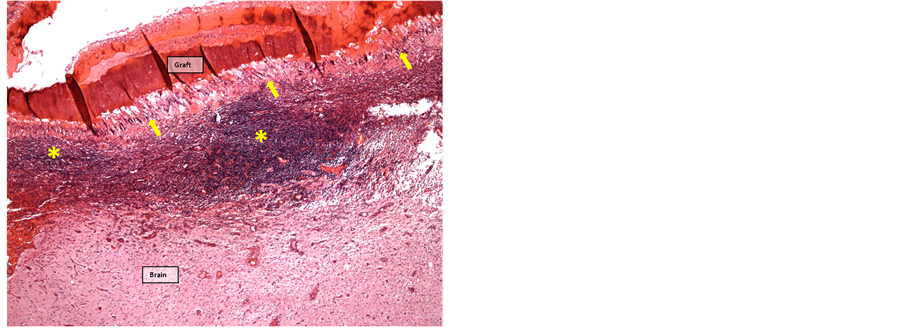

After five weeks, inflammatory changes in the fish skin graft had regressed, but a continuous layer of multinuclear giant cells enclosed the graft, gradually replacing the graft from the periphery. The layer of giant cells was surrounded by an intense infiltration of lymphocytes. The inflammatory adhesion of the leptomeninges was still present (Figure 9 and Figure 10).

Figure 9. Graft 5 weeks postoperatively surrounded by multinuclear giant cells (arrows). A layer of mononuclear leukocytes (*) infiltrate subarachnoid space through the underlying pia mater (HE-staining, 4× objective).

Figure 10. Graft 5 weeks postoperatively surrounded by multinuclear giant cells (yellow arrows) and mononuclear infiltrates (*). Early organization and angioneogenesis (red arrows) (MP-staining, 4× objective).